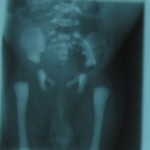

Asphyxiating Thoracic Dystrophy (Jeune Syndrome)

Third male child of a consanguineous marriage with respiratory complaints.Both elder siblings died one at the age of 3 years and other at early infancy